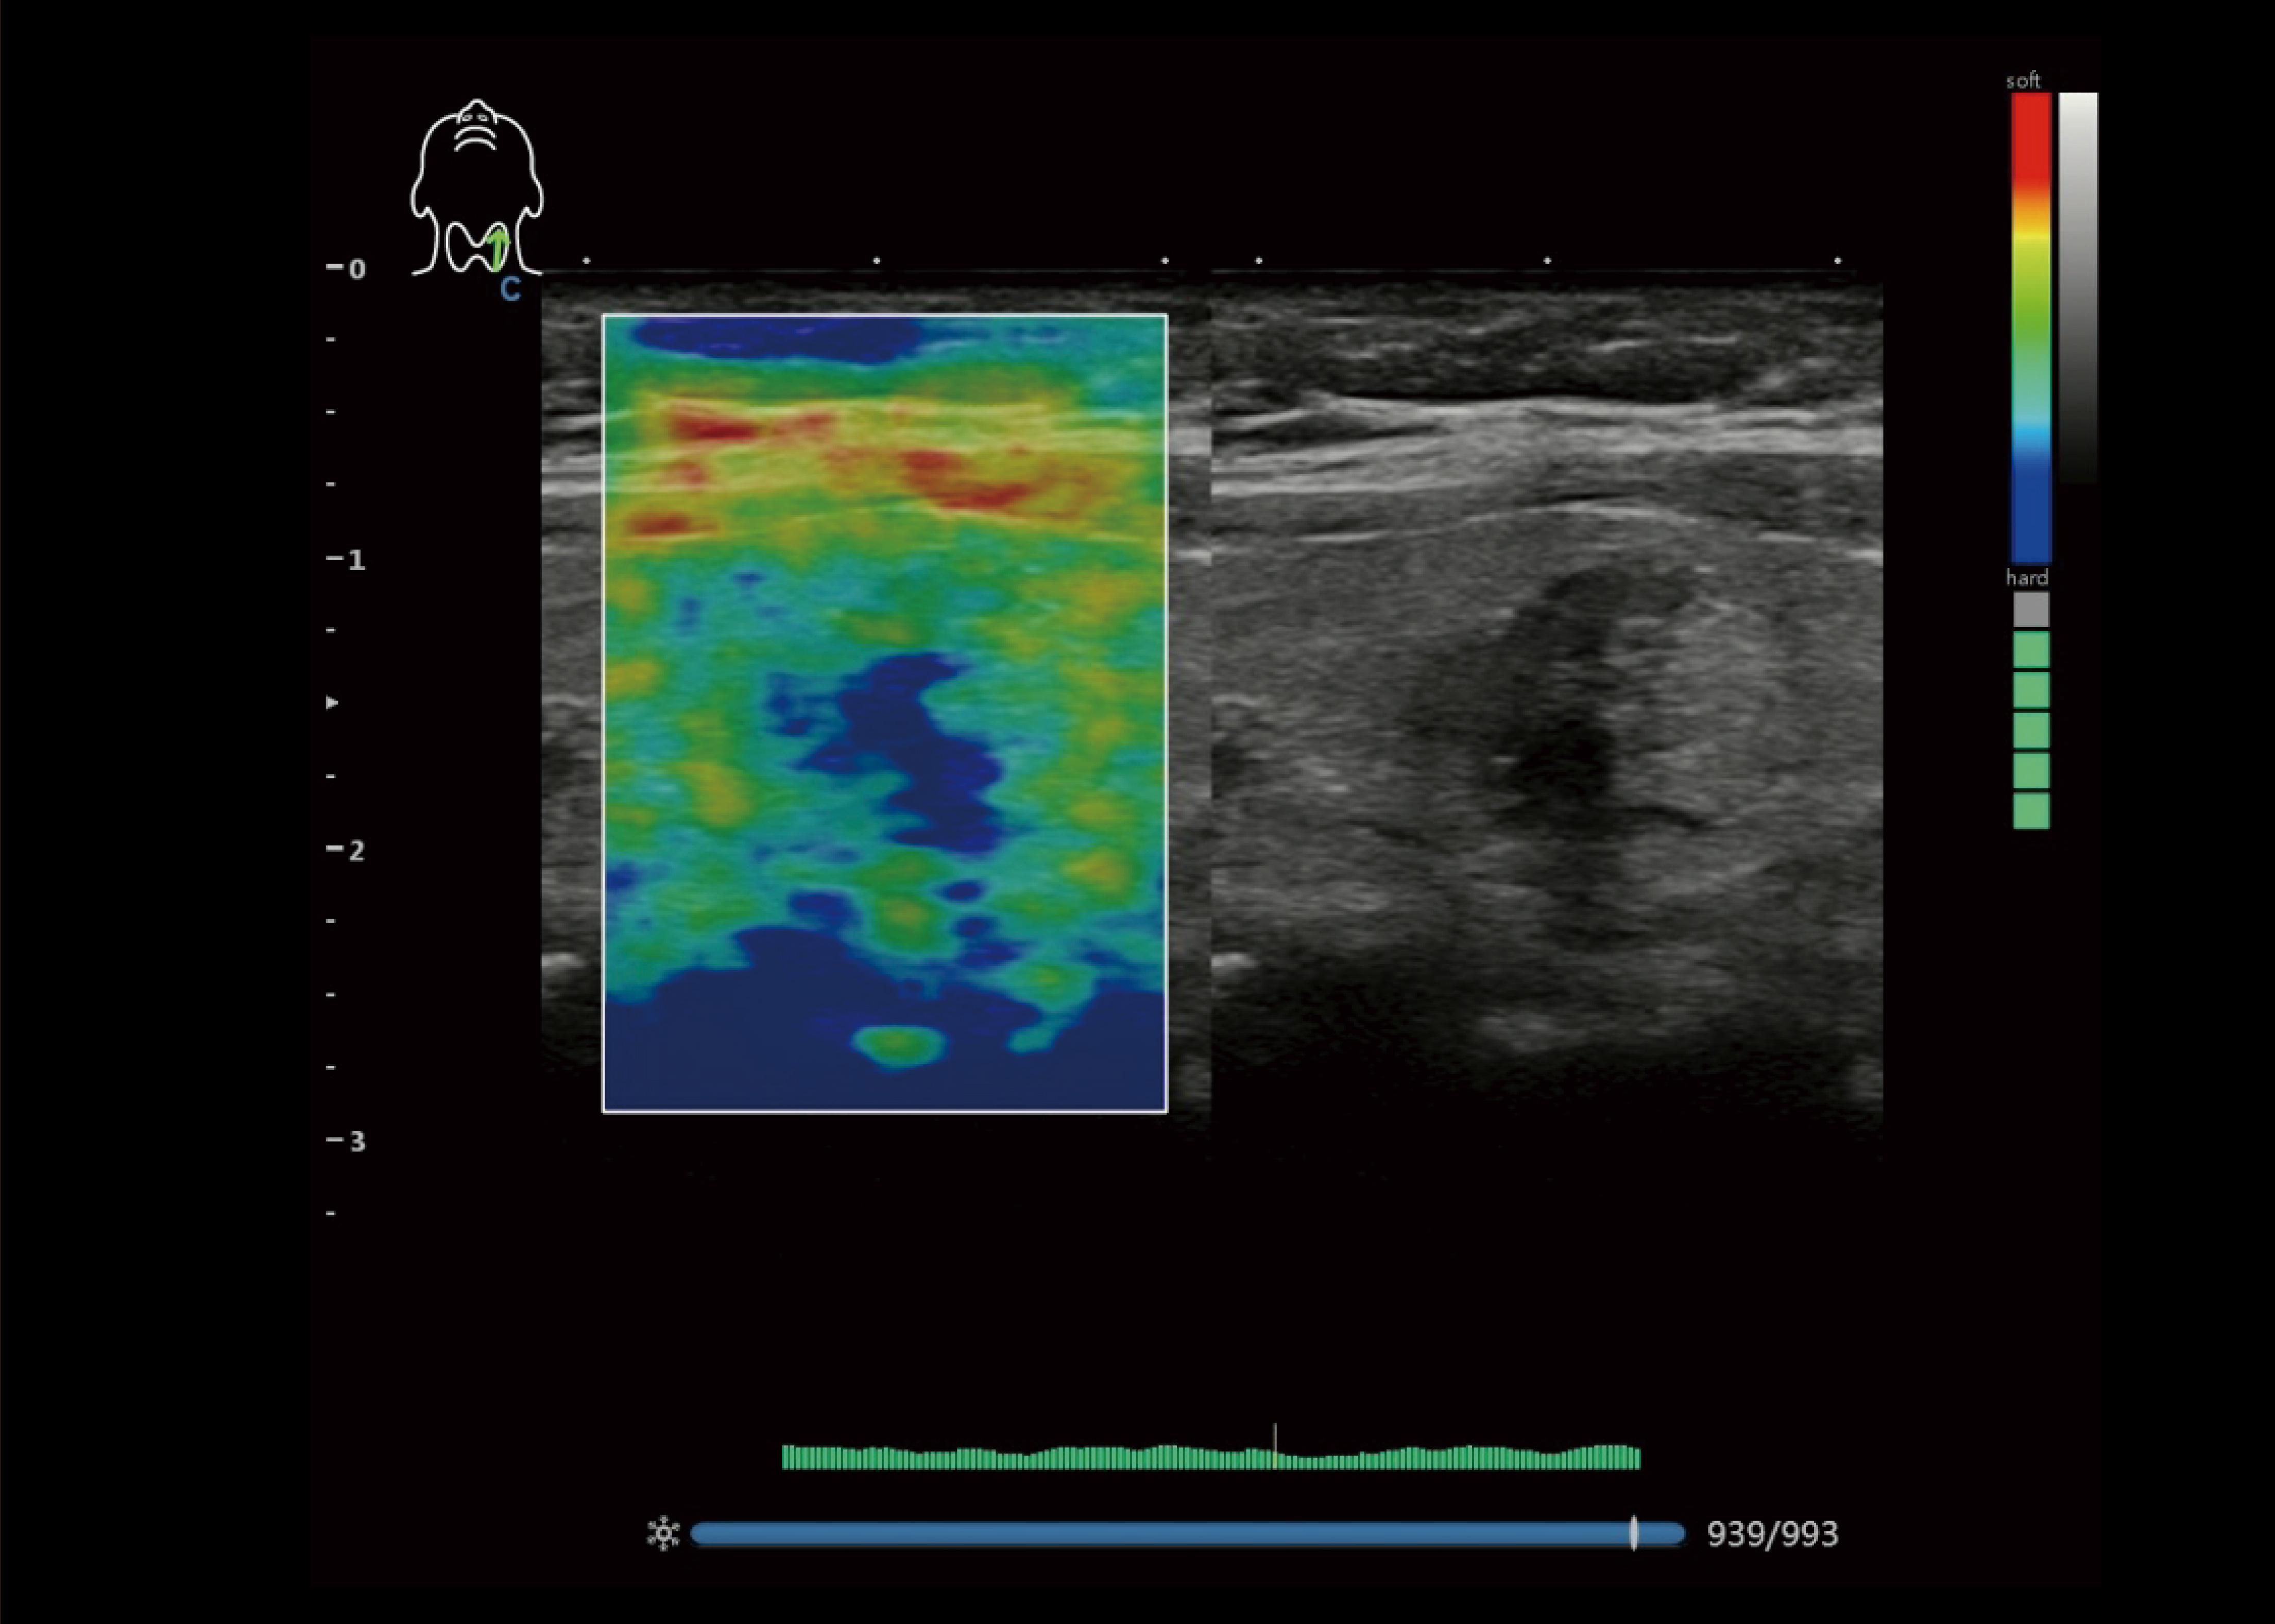

Elastographie

● Anzeige der Elastizität verschiedener Gewebe in verschiedenen Farben.

● Bereitstellung von mehr klinischen Informationen, insbesondere für die Brust Tumor, Schilddrüse, Leber und Prostata (einschließlich linearer, konvexer) transvaginale Sonde.

● Die Messung des Dehnungsverhältnisses ergibt quantitativ das Verhältnis zwischen der durchschnittlichen Dehnung der ausgewählten Region und der nahe gelegene normale Geweberegion.